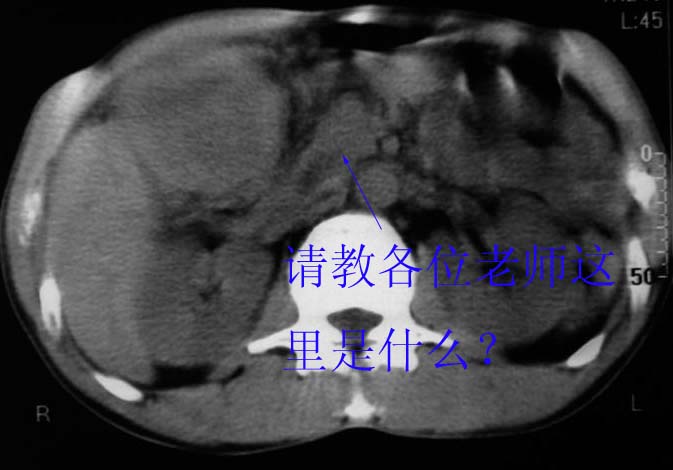

谢谢各位老师的指导学生还有几处不明白,请教。

作者: meng-msp001    时间: 2007-1-12 02:12

没有增强!只能考虑左叶内侧段巨块型肝癌(外生型)可能性大;胆囊呢?不除外胆囊癌累及肝脏

考虑:肝左内叶巨块型癌,主动脉旁淋巴结转移.(有一层面似见胆囊受压.)